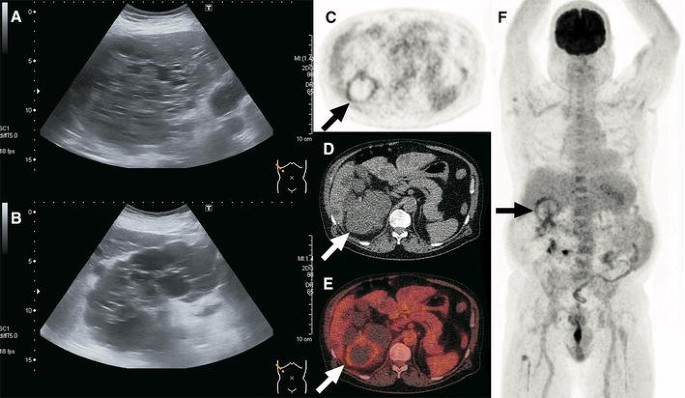

A 68-year-old woman with ADPKD presented with a feeling of general malaise that had been increasing over the course of 2 weeks. Nocturnal sweats were also present in the last week. There was no fever or abdominal pain. Blood tests showed a CRP level of 242 mg/L and a white blood cell count of 15.8 × 109/L. Blood cultures were positive for Escherichia coli and urine cultures were positive for Klebsiella pneumoniae. The patient was admitted with a differential diagnosis of urosepsis or an infection of her abdominal aortic endograft. Despite intravenous treatment with cefuroxime for 4 days, infectious parameters remained high (CRP level of 228 mg/L). To find the source of infection, a contrast enhanced CT scan of the abdomen was ordered. Axial arterial phase (a) and portal-venous phase (b) full-dose CT scans showed multiple liver cysts that were otherwise unremarkable. Because CT failed to identify any site of infection, an FDG-PET/CT scan was ordered. Axial FDG-PET (c) fused FDG-PET/CT (d), and coronal maximum intensity projection FDG-PET (e) showed pathologic FDG uptake of the wall of a cyst in segment seven of the liver (arrows), in keeping with cyst infection. No pathologic FDG-avid foci were detected elsewhere. The antibiotic regimen was changed to ceftriaxone for better cyst penetration. CRP levels decreased to 49 mg/L in 4 days. The patient was sent home in good condition with a subsequent course of ciprofloxacin